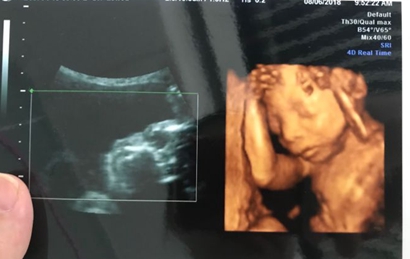

四维彩超是目前比较流行的孕检之一,四维能对胎儿头面部立体成像,可清晰显示胎儿的状态,网上很多四维是女孩但是却生了男孩的案例,那么四维女孩翻盘几率大吗?更多关于生男生女的相关内容尽在孕宝网。

四维一般都是二十四周以后照的,这么大的孕周出错的机会还是比较小的,虽然不是百分之百准确的,但是出错的概率还是会比较少的,大部分情况都是不会出现翻盘的情况,四维超声同其它超声检查相比,可以实时观察人体内部器官的动态运动,也能准确地分辨出胎儿的性别。虽然四维彩超能够看清胎儿的性别,但在检查过程中,为了避免透露胎儿的性别,医生会主动的回避胎儿的性别特征以及下半身,因此最好找熟人的医生做这样才能更准确知道宝宝的性别。